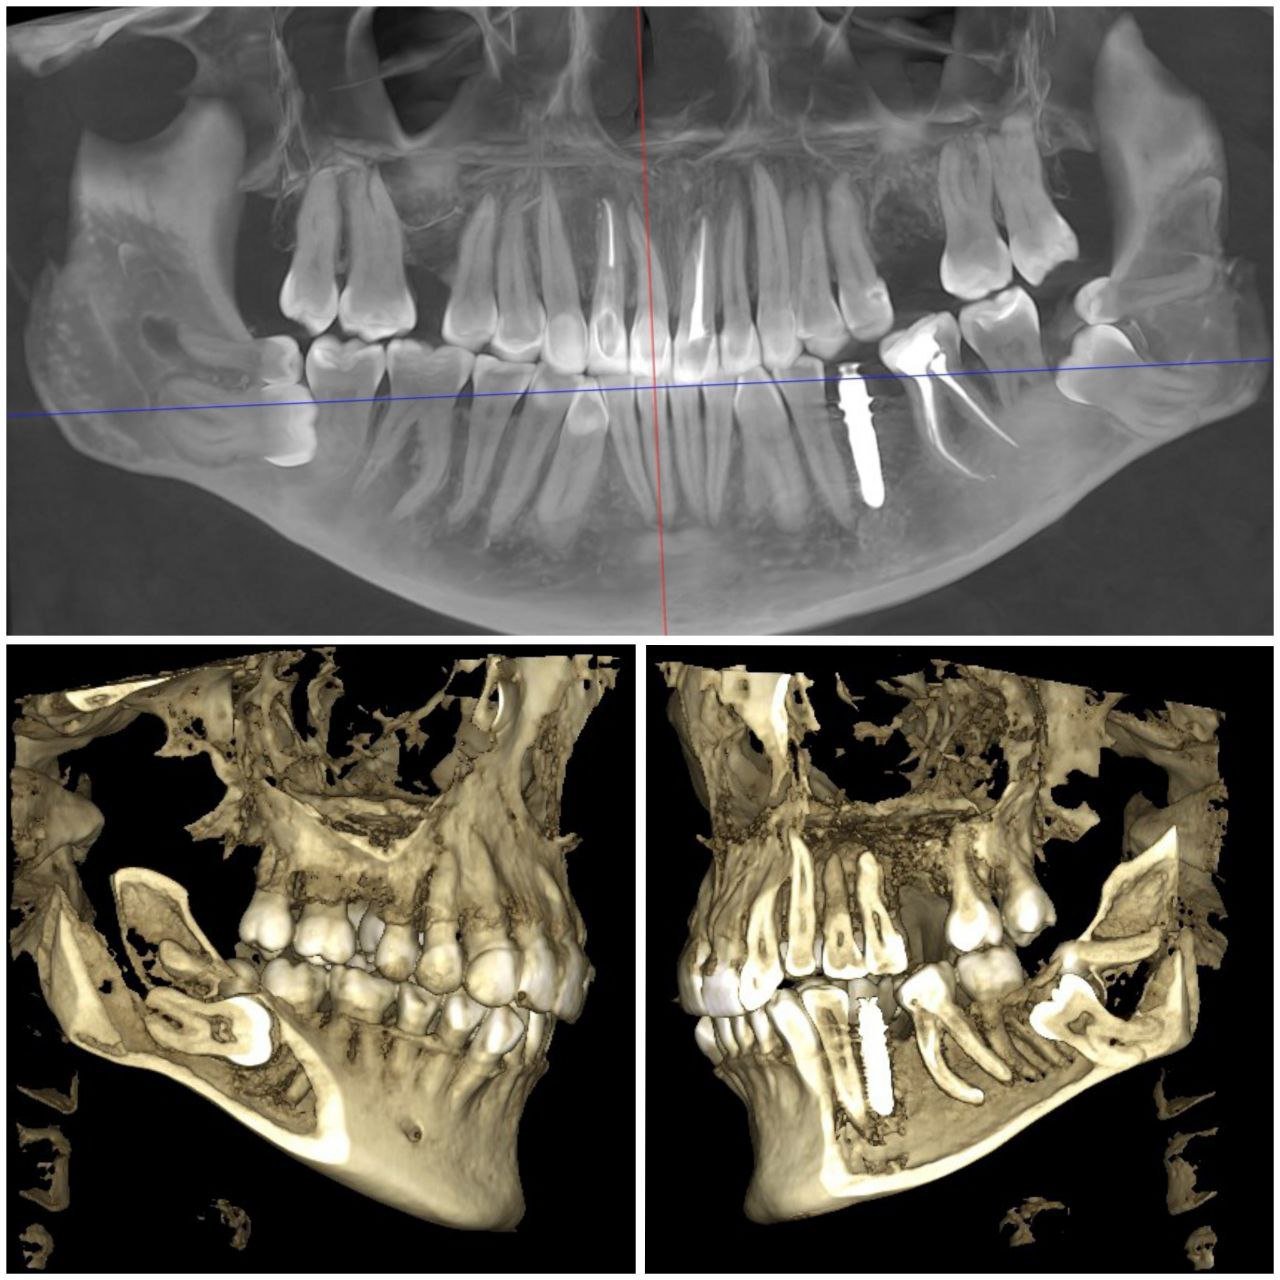

- Самостійно вибрати зубний імплант — це нерозв’язне завдання для неспеціаліста. Підбір імплантаційної системи слід довірити досвідченому лікарю, який проведе 3D діагностику і запропонує відповідні варіанти реконструкції посмішки.

Ключ до успішної імплантації — точна діагностика. В арсеналі “ДентЛюкс” є один із найкращих КТ-апаратів в Україні— PLANMECA VISO G7.

Завдяки 3D-діагностиці імпланти встановлюються з ідеальною точністю. Результат — безпечно, комфортно та надовго.